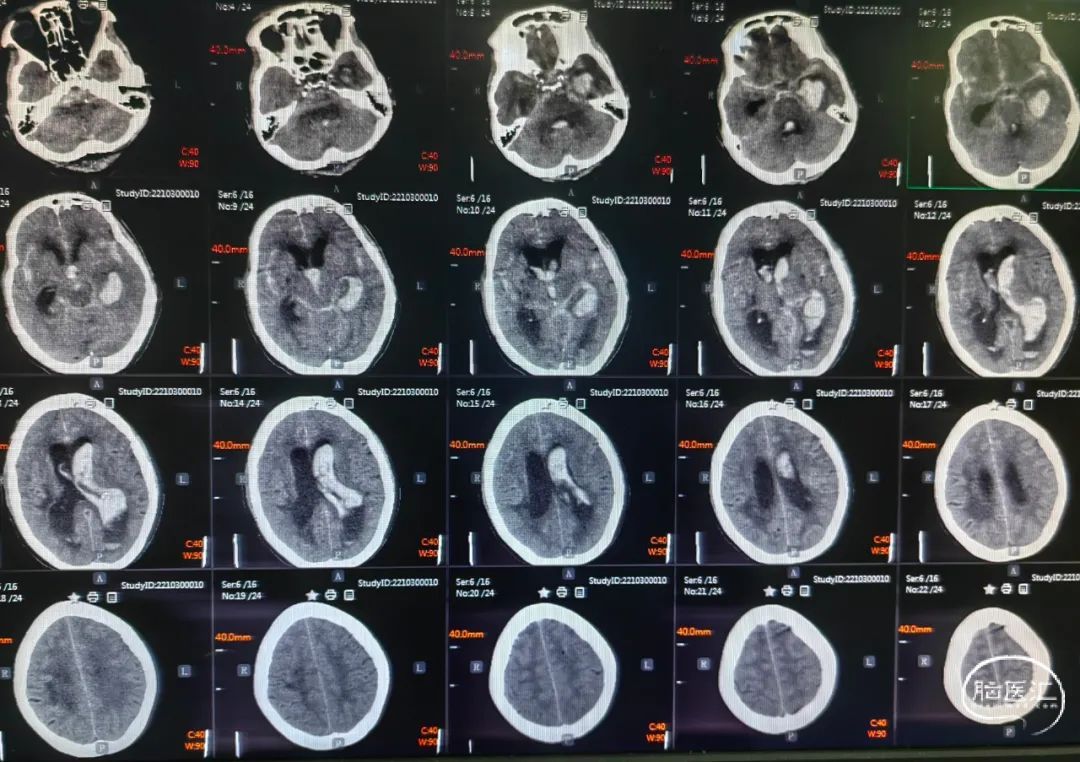

术前头颅CT提示:左侧基底节区脑出血破入脑室系统。

术后一周头颅CT提示:脑室系统积血较前明显减少。

卧床一周胸部CT:双肺片状炎症。